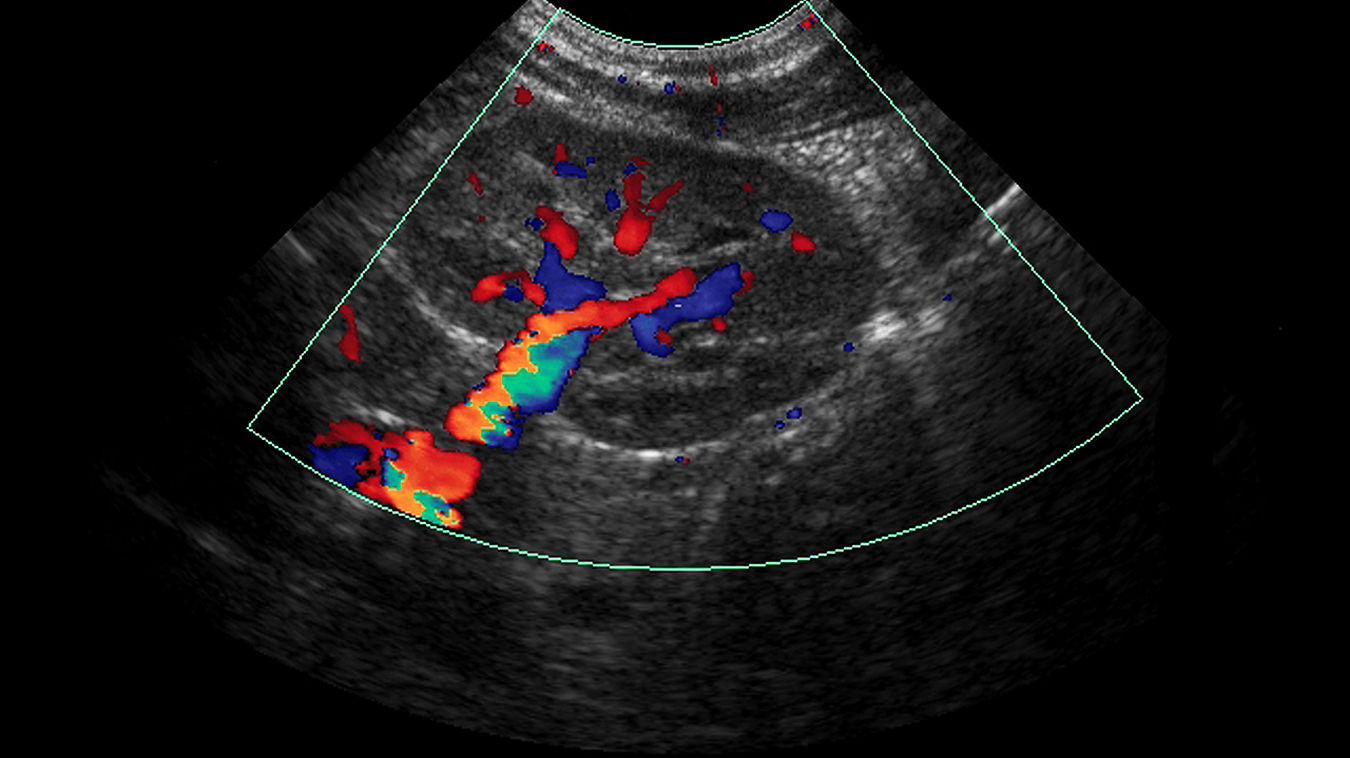

Режими УЗД, що застосовуються

Для дослідження артерій використовуються різні режими УЗД, кожен з яких дає можливість отримати конкретну інформацію про стан судин. Режими УЗД судин:

- В-режим — дозволяє оцінити діаметр судини, її форму, стан стінки та наявність звужень чи перекриттів;

- ЦДК (кольоровий доплер) — визначає напрямок кровотоку, допомагаючи виявити перешкоди, такі як бляшки, а також визначити дисекцію артерії;

- PW-доплер (імпульсний доплер) — дає можливість виміряти швидкість кровотоку;

- CW-доплер (постійнохвильовий доплер) — оцінює високошвидкісні потоки крові, зокрема в місцях стенозу чи оклюзії судин.

Режими дозволяють комплексно оцінити стан судин і кровотоку, що є необхідним для діагностики різноманітних порушень. Розшифровку результатів УЗД судин проводить гематолог.